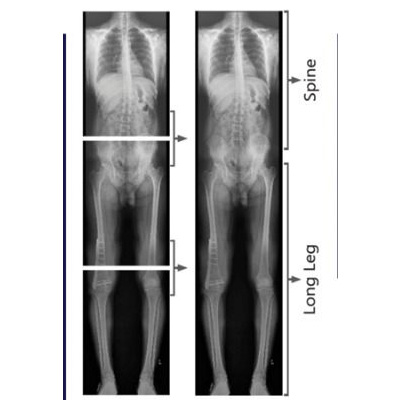

Whole Spine & Long Leg (Image Stitching)

SR Scanning Center is equipped with advanced Image Stitching Software. Standard X-ray plates are not long enough to capture the entire spine or the entire leg in one go. Image stitching solves this by combining multiple images into one seamless panoramic view.

Whole Spine Scanography: Essential for diagnosing and measuring Scoliosis (curvature of the spine) and Kyphosis. It allows the doctor to measure the Cobb angle accurately for treatment planning.

Long Leg Scanogram: Used to measure Limb Length Discrepancy (difference in leg lengths) and mechanical axis alignment. This is vital for planning corrective osteotomy surgeries and total knee replacements to ensure perfect alignment.

Key Highlights

• Full-length imaging of Spine (Scoliosis Study).

• Full-length imaging of Legs (Scanogram).

• Seamless digital stitching for accurate measurement.

• Essential for orthopedic surgical planning.